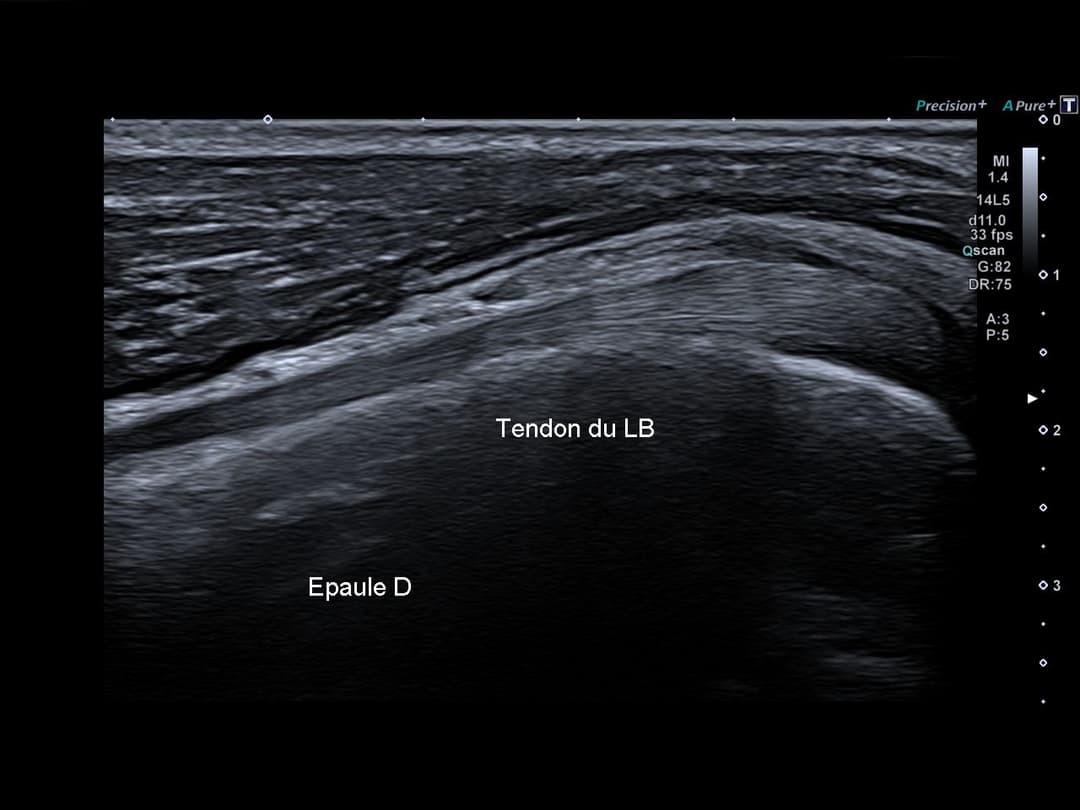

Absence d'épanchement dans la gaine synoviale de la portion antérieure du long biceps

Tendon du long biceps centré dans le sillon intertuberculaire